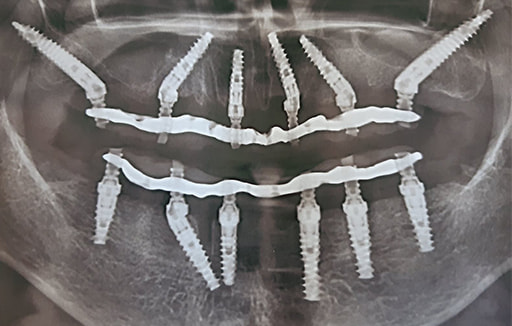

Решение

После установки дентальных имплантатов Noris Medical по технологии All-on-6 на верхней и нижней челюсти